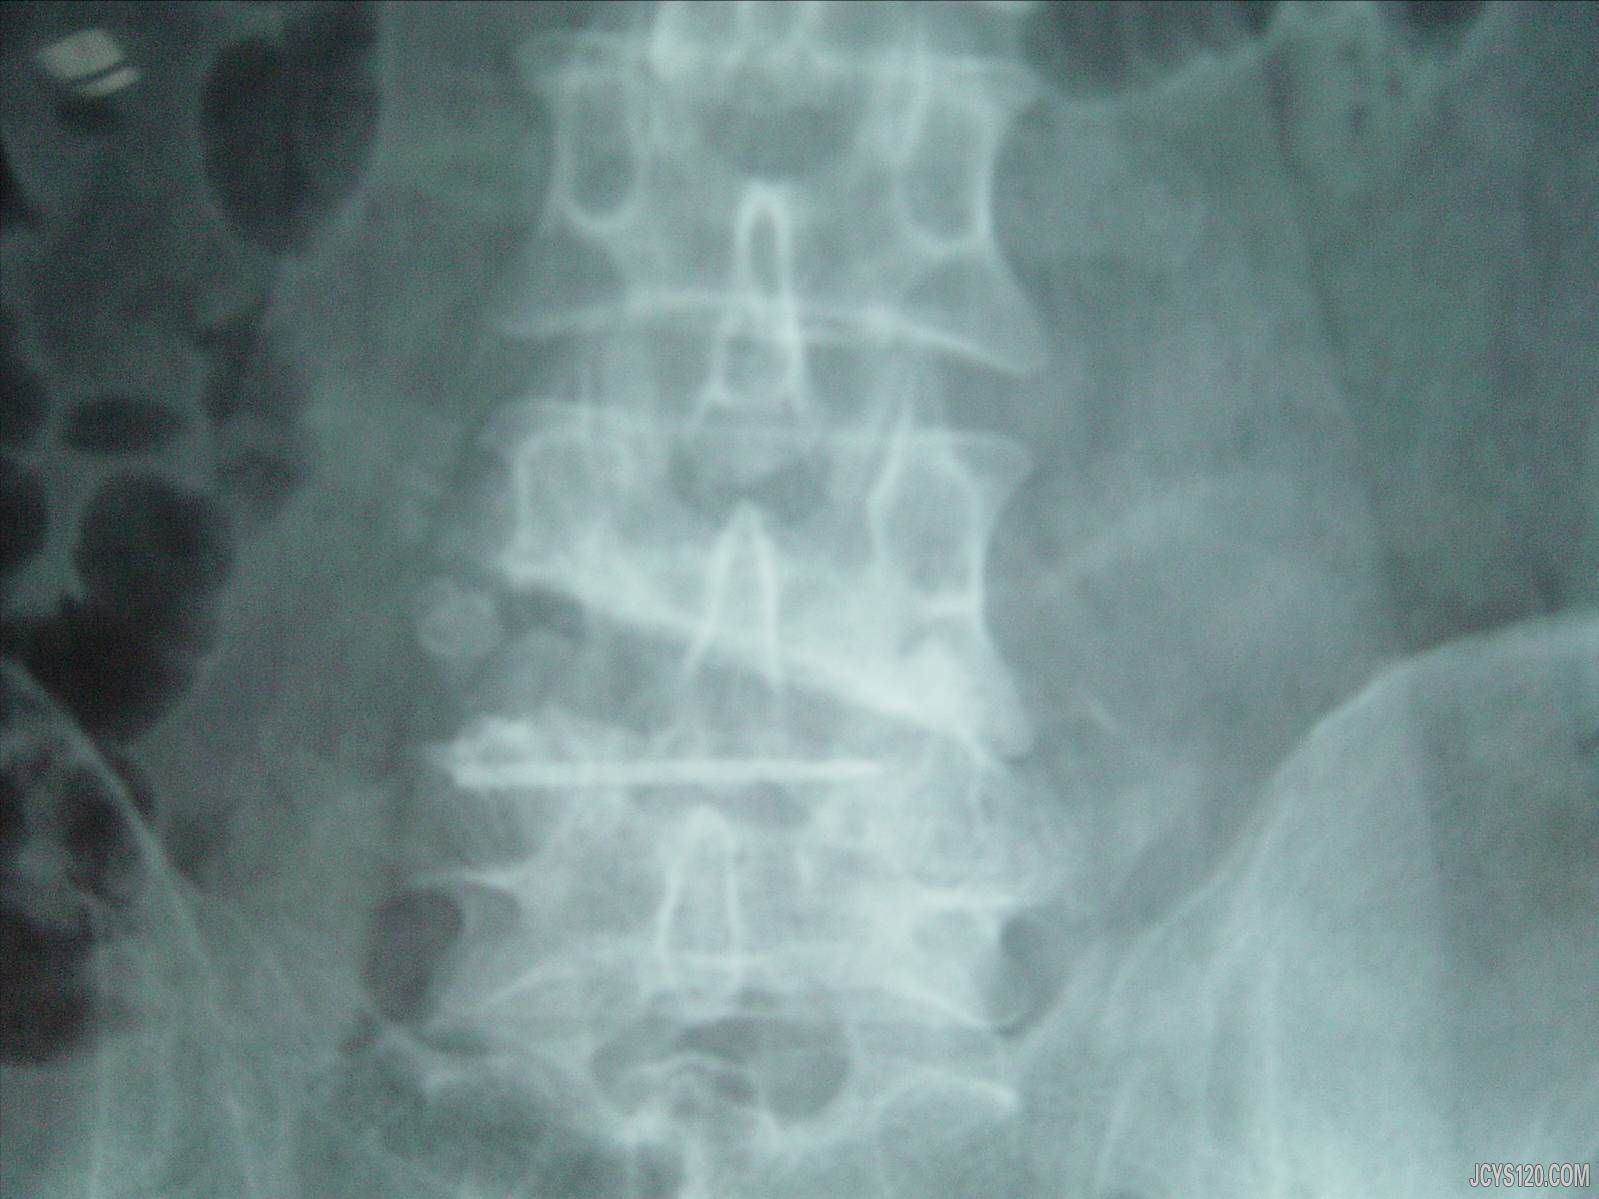

• 腰痛伴踝肘关节破溃 新人帖 attach_img

• 男,54岁,腰痛1年,加重1个月。近半年出现踝肘关节痛痛,伴破溃,露出白色豆腐渣样物。腰部压痛点贴针头拍摄腰椎正位片见腰4终板下骨破坏。请诊断。  阅读全文>